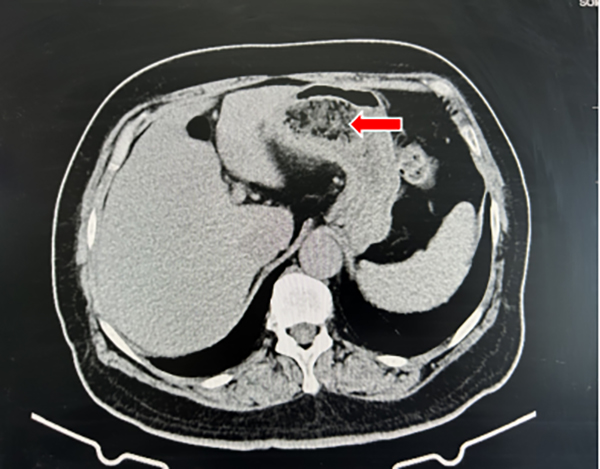

图 1 腹部CT示胃内混杂密度团块